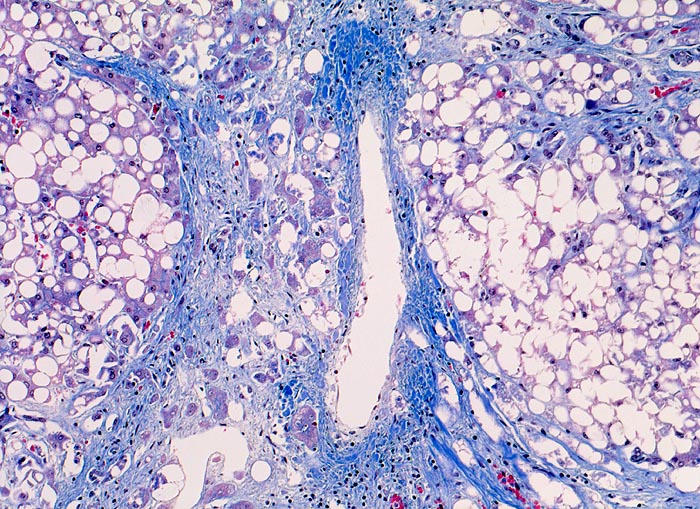

Meist findet sich eine grobtropfige oder gemischttropfige Verfettung des Parenchyms. Schon im Frühstadium der alkoholischen Steatohepatitis kann eine perizelluläre Maschendrahtfibrose, perisinusoidale und perivenuläre Fibrose mit Beginn in der Zone 3 festgestellt werden. Die Kombination von perivenulärer und perizellulärer (> 1096) Fibrose wird bei starker Ausprägung mit Arealen von dichter Kollagenfaserbildung auch als zentrale sklerosierende hyaline Nekrose bezeichnet. Wenn der Vernarbungsprozess fortschreitet, kann die perivenuläre Fibrosezone mit vernarbten Portalfeldern verschmelzen. Zentralvenen verschwinden oder sind stark in der Anzahl reduziert. Eine Phlebosklerose oder Obliteration der Zentralvenen kann hinzukommen. Breite Bänder von fibrotischem Gewebe mit Ductulusproliferationen und gemischtem Entzündungsinfiltrat umgeben die bei alkohlischer Zirrhose meist kleinen Regeneratknoten (=mikronoduläre Leberzirrhose mit Regeneratknoten von weniger als 3mm Durchmesser). Bei längeren Abstinenzphasen kann sich aufgrund der gesteigerten Regeneration auch eine gemischtknotige Zirrhose ausbilden. Ein gleichzeitiges Vorliegen einer Steatose oder Steatohepatitis (Steatose+neutrophile Granulozyten) in einer alkoholischen Leberzirrhose signalisiert in der Regel einen fortgesetzten Aethylabusus. Typisch für alkoholtoxische Leberschädigung sind Mallory-Denk Körperchen (> 3021), Megamitochondrien (> 3022) und eine Zellschwellung (=Ballonierung) aufgrund einer gestörten Albuminausschleusung. Oft können mässige Mengen von Hämosiderinablagerungen vor allem in den Kupffer Zellen nachgewiesen werden. Weitgehend identische morphologische Veränderungen wie bei der aethylischen Leberschädigung finden sich auch bei der nicht alkoholischen Steatohepatitis (NASH) d.h. bei Patienten, die keinen oder nur wenig Alkohol konsumieren.

Morphologische Merkmale:

• Zerstörte Läppchenarchitektur mit diffusem feinknotigem Umbau des Leberparenchyms.

• Breite Fibrosebänder mit Ductulusproliferation und gemischter Entzündung.

• Perivenuläre Fibrose und perizelluläre Maschendrahtfibrose in Zone 3.

• Verminderte Anzahl Zentralvenen.

• Überwiegend makrovesikuläre, teils gemischttropfige Verfettung der Leberzellen.